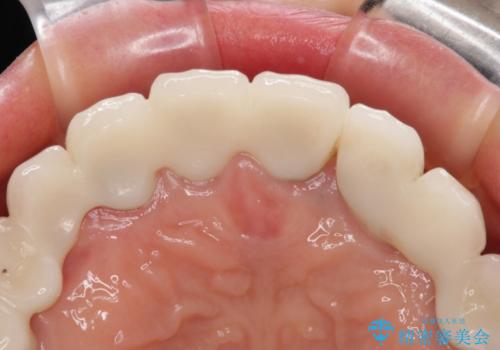

- 割れていると言われて放置してしまった歯や、前歯のデコボコなどが気になるとのことで来院された患者様です。

左上の歯は割れてしまっており、抜歯のうえインプラント治療が必要であり、他にも抜歯の必要な歯がある状態でした。

上顎はほぼ全ての歯をセラミッククラウンにて補綴治療を行う必要があるため、気になるデコボコや深い咬み合わせを改善するために下顎と上顎の臼歯部の矯正治療を行うこととしました。